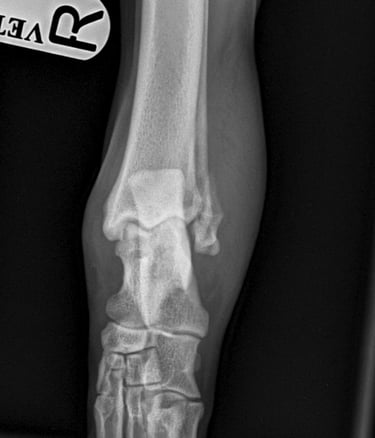

Orthogonal xrays reveal a lateral malleolus fracture (Fig.1 and 2), stress views and palpation revealed stable joint with no affection of collateral ligaments but due to the fracture there is some degree of rotational instability. Surgical stabilization is strongly advised as Buddy is a 40 kg patient.

Lateral approach to the talocrural joint reveals severe oedema and bruising, 1.2mm IM pin placed in a distal to proximal fashion, 0.75mm cerclage wire used to create a figure-of-8 tension band. 1.4mm pin placed parallel to the talocrural joint from lateral to medial (Fig 3 and 4).

Lateral malleolus fractrure – Golden retriever, 2y, male